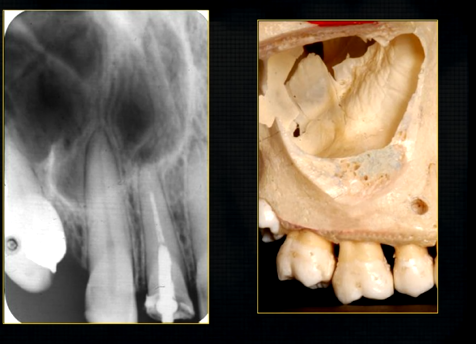

periapical radiograph → posterior maxilla

radiolucent maxillary sinus and radiopaque floor

radiopaque shadow cast by zygoma, hollowed out by maxillary sinus

lower end of the dense, zygomatic bone

posterior aspect of the maxilla - smooth round tuberosity

1st image taken using the bisected angle technique

2nd was taken using the geometrically accurate, paralleling technique

upper image is geometrically distorted

shadow caused by zygoma

this was taken using the bisected angle technique

x ray beam was directed below the zygoma

very lower of the zygoma is seen - projected above the apices

pterygoid hammulus - supports the muscles of the soft palate

coronoid process of the mandible